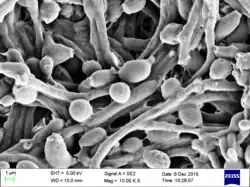

| Candida albicans visualized using scanning electron microscopy. Note the abundant hyphal mass. | |

C. albicans is commonly used as a model organism for fungal pathogens.[19] It is generally referred to as a dimorphic fungus since it grows both as yeast and filamentous cells. However, it has several different morphological phenotypes including opaque, GUT, and pseudohyphal forms.[20][21] C. albicans was for a long time considered an obligate diploid organism without a haploid stage. This is, however, not the case. Next to a haploid stage C. albicans can also exist in a tetraploid stage. The latter is formed when diploid C. albicans cells mate when they are in the opaque form.[22] The diploid genome size is approximately 29 Mb, and up to 70% of the protein coding genes have not yet been characterized.[23] C. albicans is easily cultured in the lab and can be studied both in vivo and in vitro. Depending on the media different studies can be done as the media influences the morphological state of C. albicans. A special type of medium is CHROMagar Candida, which can be used to identify different Candida species.[24][25]

C. albicans exhibits a wide range of morphological phenotypes due to phenotypic switching and bud to hypha transition. The yeast-to-hyphae transition (filamentation) is a rapid process and induced by environmental factors. Phenotypic switching is spontaneous, happens at lower rates and in certain strains up to seven different phenotypes are known. The best studied switching mechanism is the white to opaque switching (an epigenetic process). Other systems have been described as well. Two systems (the high-frequency switching system and white to opaque switching) were discover by David R. Soll and colleagues.[41][42] Switching in C. albicans is often, but not always, influenced by environmental conditions such as the level of CO2, anaerobic conditions, medium used and temperature.[43] In its yeast form C. albicans ranges from 10 to 12 microns.[44] Spores can form on the pseudohyphae called chlamydospores which survive when put in unfavorable conditions such as dry or hot seasons.[45]